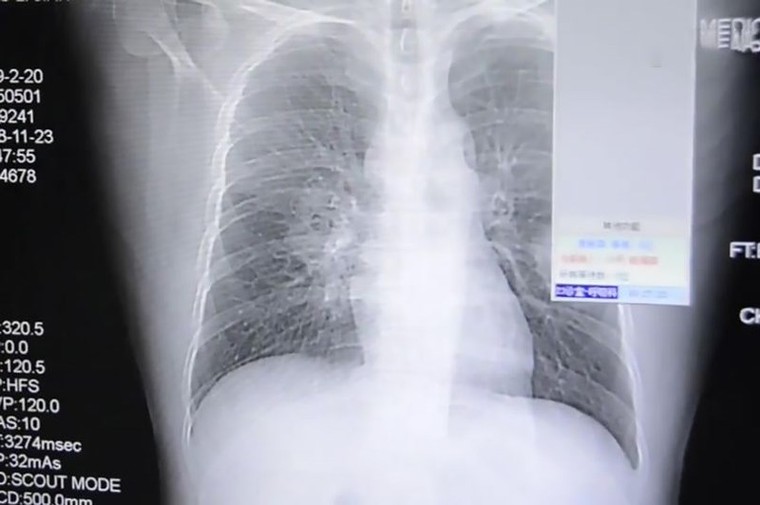

Phim chụp X-quang phổi của người đàn ông. Ảnh: ASIAWIRE

Được biết, sau khi đi làm về, thay quần áo, người đàn ông này thường đưa vớ lên mũi ngửi sau khi cởi nó ra khỏi chân. Kết quả là phổi ông ta bị nhiễm một loại nấm thường có trong giày dép, đã theo đường thở đi vào phổi.

Sau một triệu chứng khó thở, người đàn ông được đưa vào cấp cứu ở bệnh viện. Sau khi chụp X-quang, các bác sĩ xác nhận ông ta đã bị nhiễm trùng phổi nghiêm trọng. Hiện ông ta đang được giữ lại bệnh viện để điều trị.